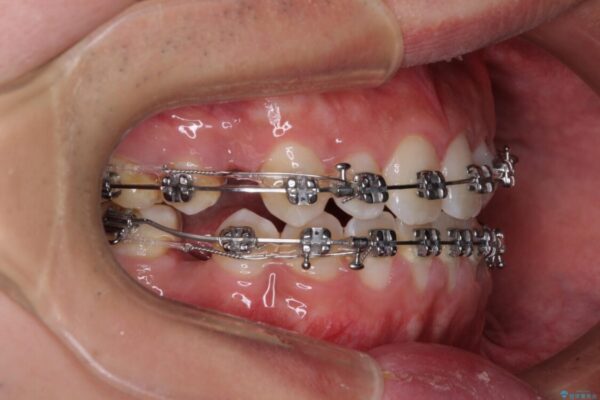

治療途中

• 口元の突出感を改善 受け口傾向の咬み合わせの抜歯矯正 治療途中画像